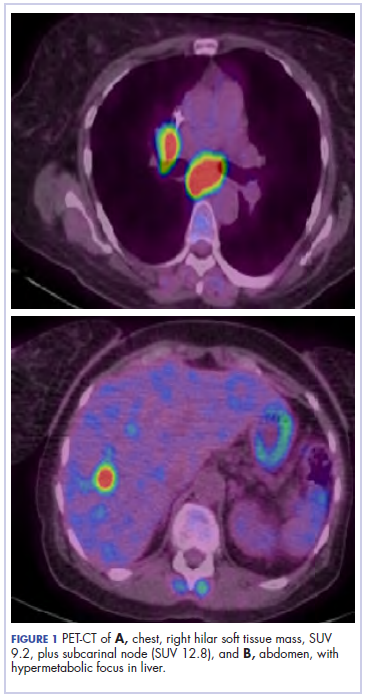

The patient resumed treatment with nivolumab after complete resolution of the rash. However, she developed grade 2 nephritis after cycle 5 with a creatinine level of 1.98 mg/dL (reference range, 0.6-1.2 mg/ dL). This was resolved after treatment with oral prednisone, at a starting dose of 1 mg/kg and tapered over 4 weeks. PET CT scans obtained after cycles 5 and 11 showed no metabolic activity in the mediastinum or the liver and markedly decreased uptake in the right lower lobe nodule, down to an SUV of 1.7 with no new nodules. An MRI of the brain was stable (Figure 2).